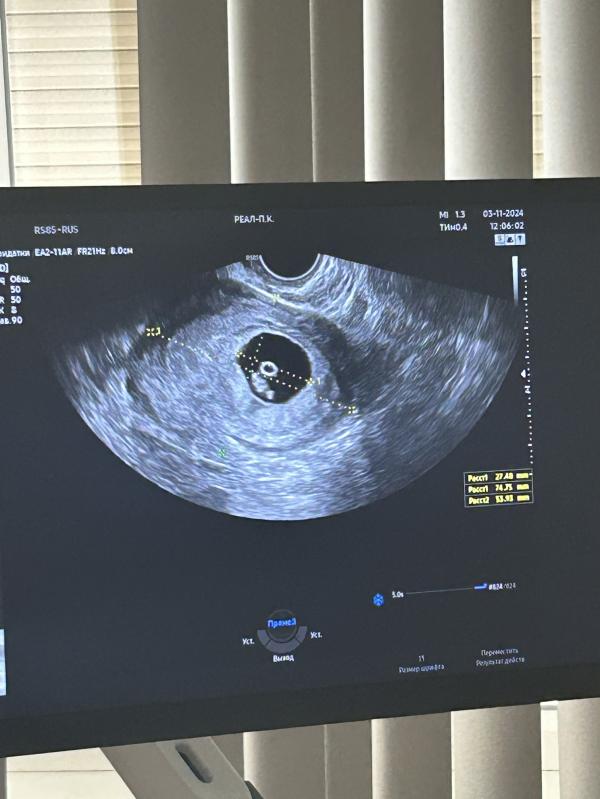

Беременность маточная , все по срокам.. ни гематом ни отслоек, даже тонуса нет , от чего светло бело-розовые выделения 2 вечера подряд не ясно , датчик узи она достала абсолютно чист был. Вот такие дела.